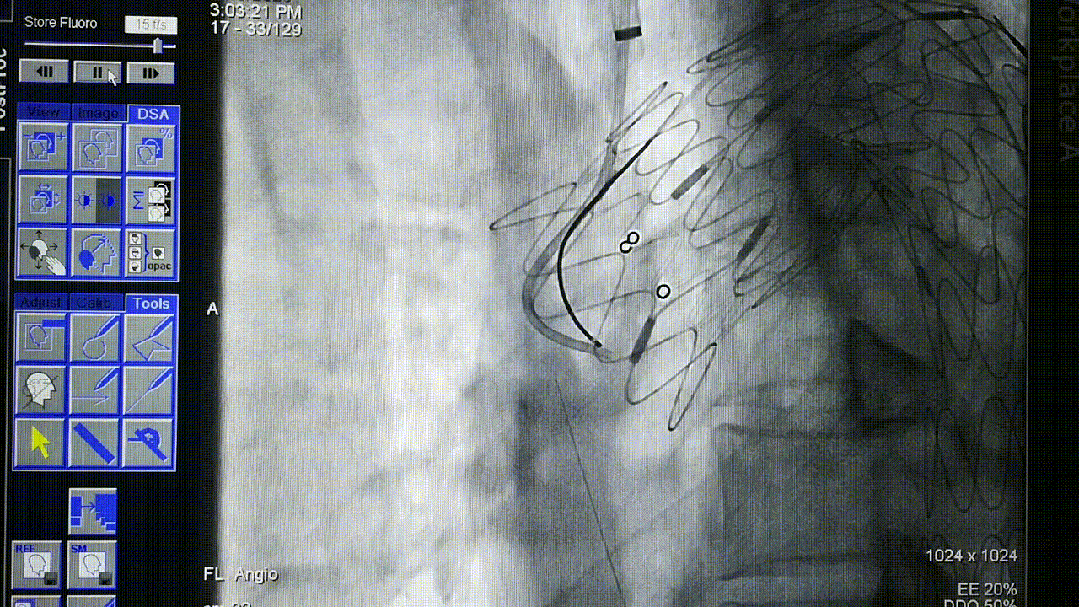

导丝破膜,各角度反复确认

各个角度反复确认,耽误时间;

转播手术过程中即便熟练团队开窗,时间不可控,导丝穿破FUSTAR